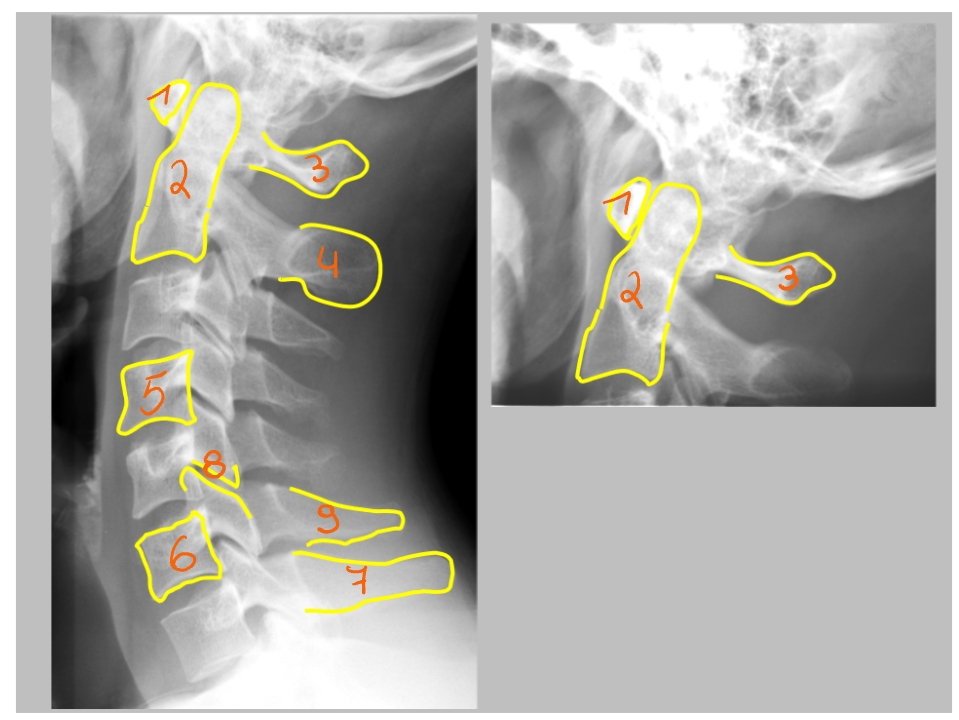

arcus anterior

arcus posterior

dens axis

processus uncinatus

corpus C4

processus uncinatus

processus spinosus C6

processus spinosus C7

corpus T1

processus transversus T1

→ T1: beste referentie => heeft grote processi transversi

arcus anterior C1

→ articulatio atlanto-axialisch-mediana = gewricht (daarrond roteren we ons hoofd)

dens axis

arcus posterior C1

processus spinosus C2

corpus C4

corpus C6

processus spinosus C7

processus articularis superior C6 & processus articularis inferior C6 → facetgewricht

processus spinosus C6

pedikel

= klein beenbrugje

ramus mandibulae

angulus mandibulae

corpus mandibulae

formamina intervertebrale

hier komen de spinale zenuwen uit

(linker beeld → linkerkaak)

schuine opname = oblique view

foramen intervertebrale C4-C5 (links)

daaruit komt spinale zenuw C5

processus uncinatus (linker)

pedikel (linker)